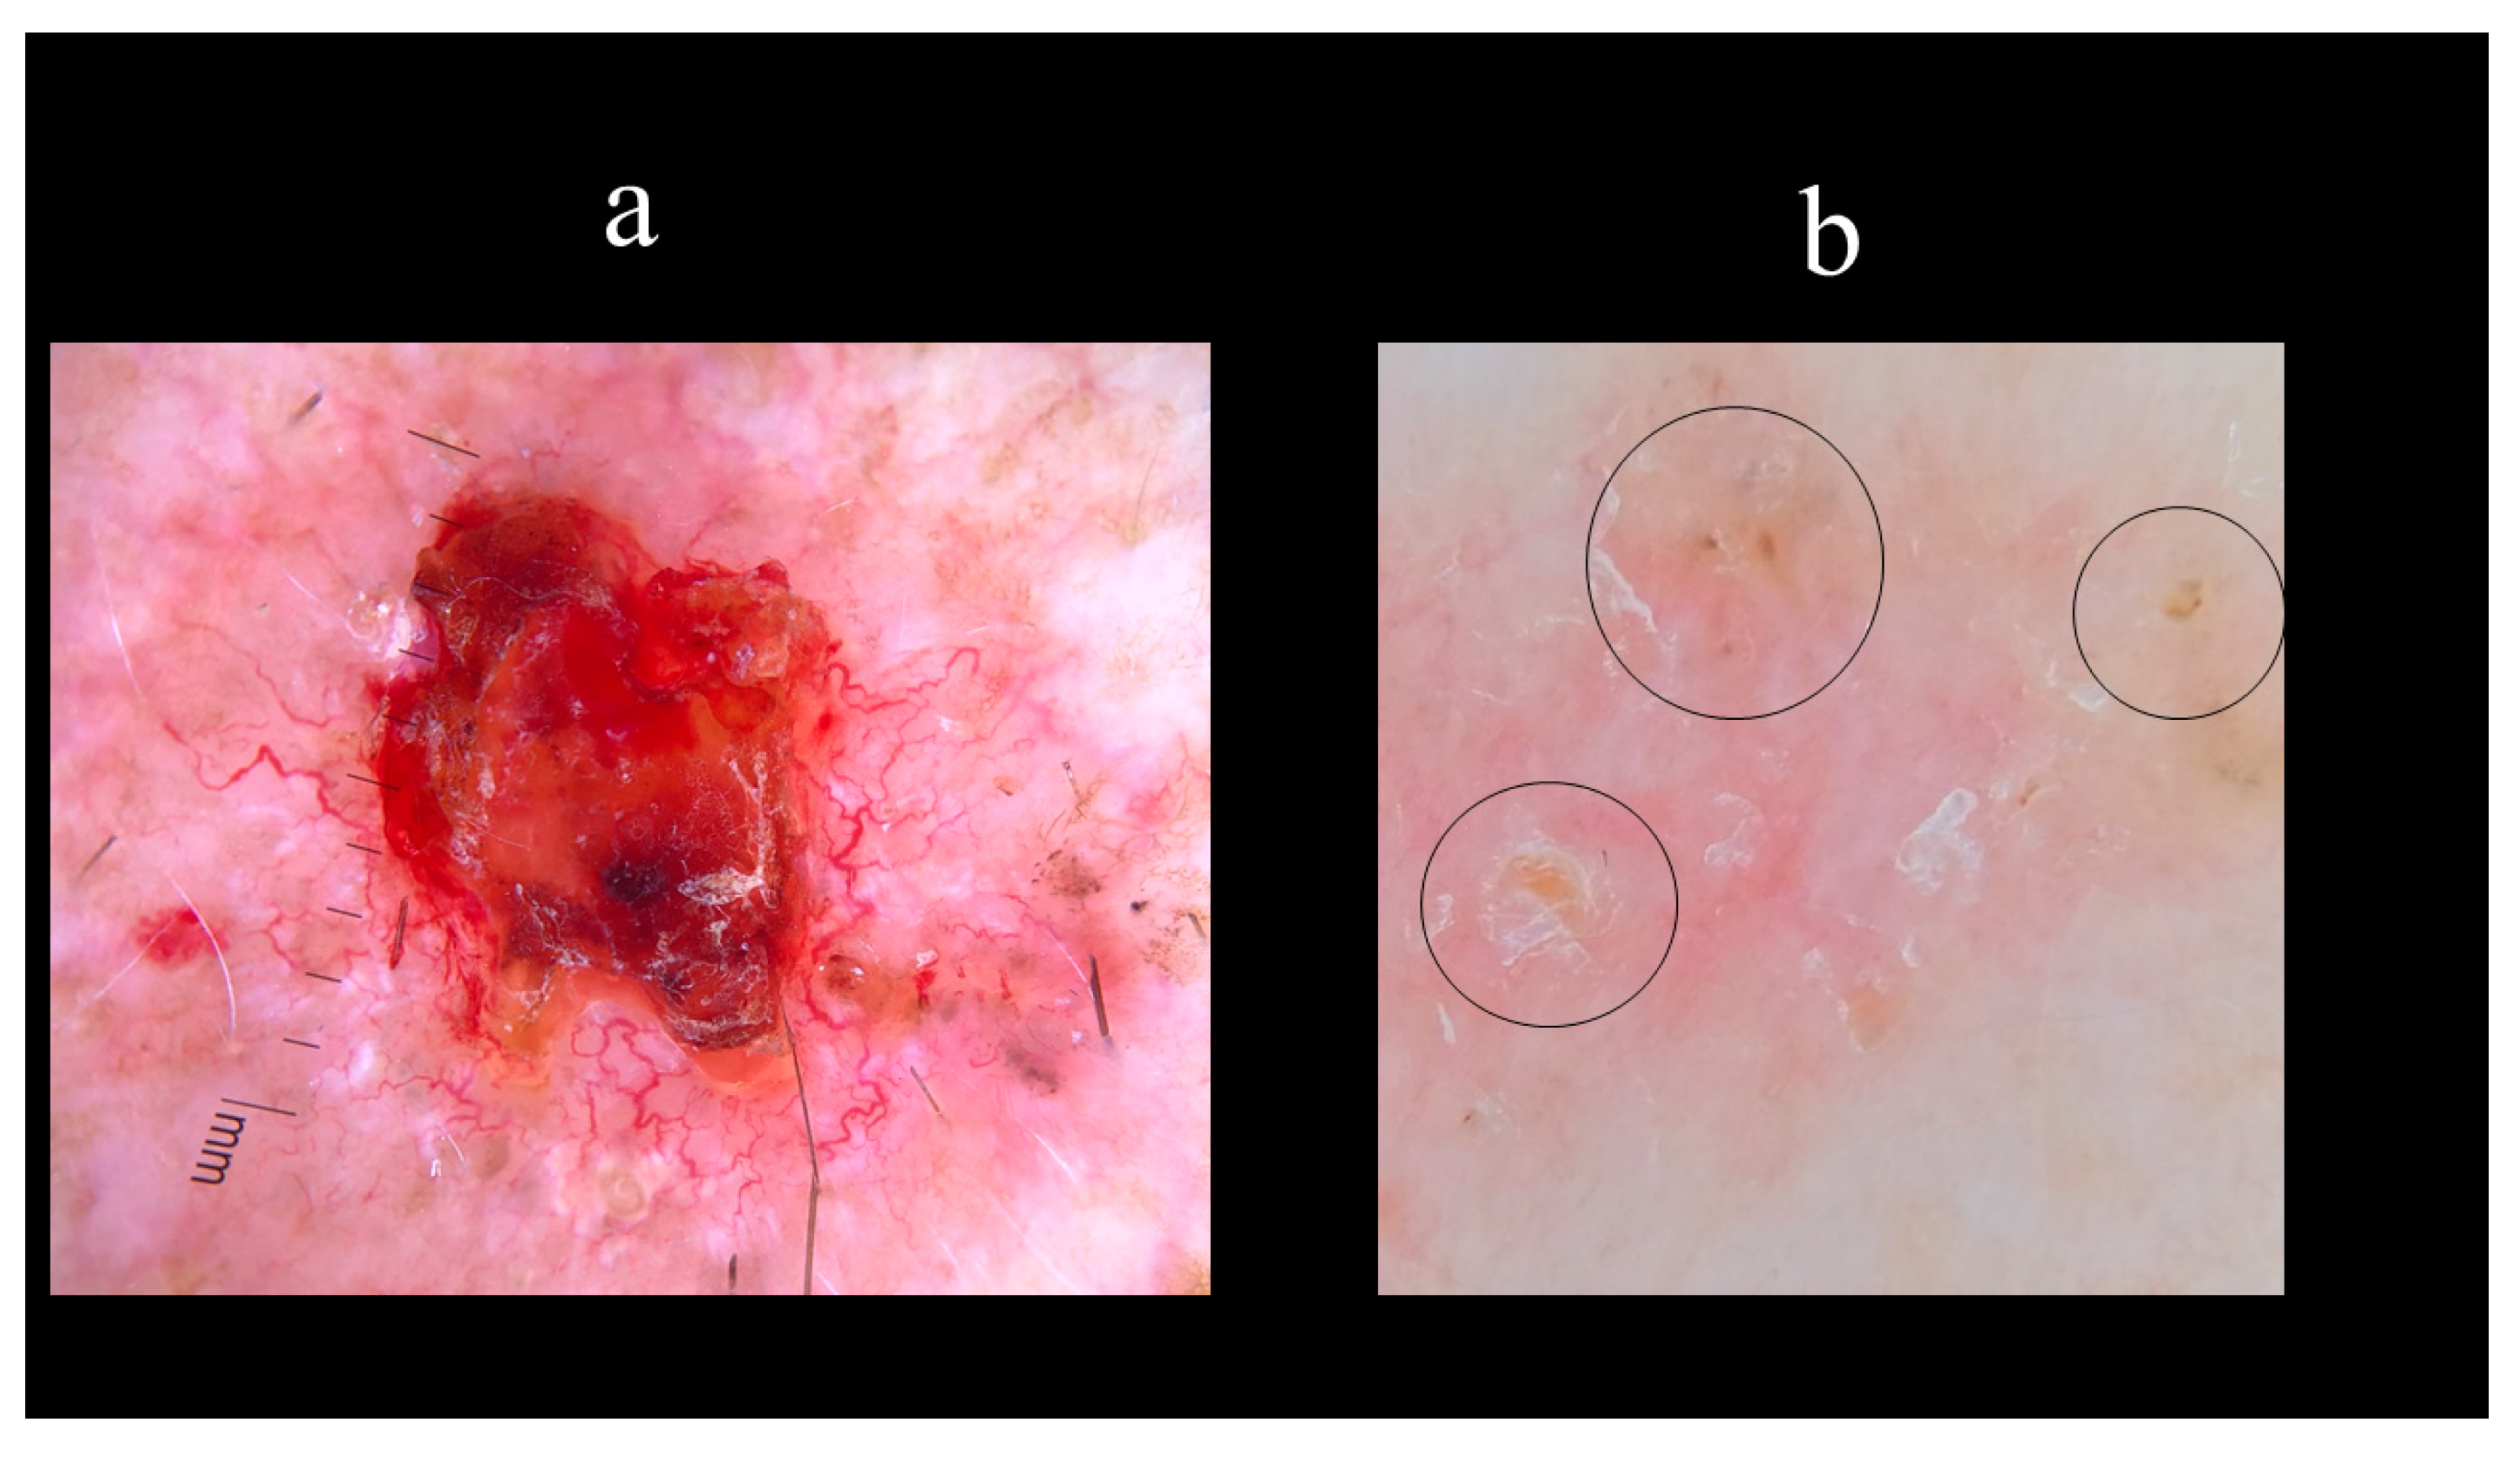

5. Dermoscopy

8.3. Curettage and Electrodessication

8.5. Photodynamic Therapy (PDT)